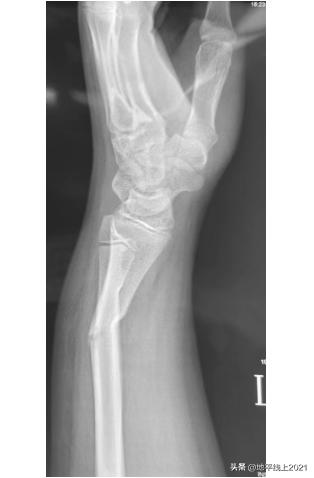

如果真的骨折了,要做手术吗? 儿童不是成人的缩小版,儿童有生长发育和自身的解剖特点——骨膜厚,塑形能力强,而且这类发生在公园和小区里的“事故”,情况通常不会太严重,家长不用太紧张。一提到骨折,许多家长会联想到“做手术”,其实可能 “打石膏” 就够了。下图是一位13岁的男孩,桡骨远端 (可简单理解为“手腕”) 骨折,成角畸形,有医生建议手术治疗,钢板固定。 我们推荐在局部麻醉下,牵引复位,用夹板固定,也取得了很好的效果。 只需一周复诊,调整夹板或者石膏。